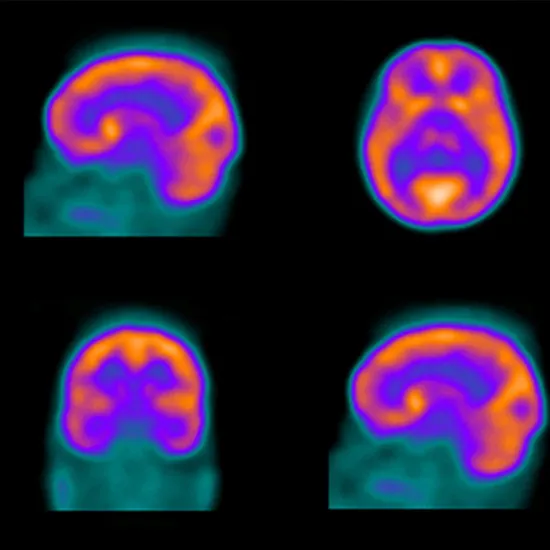

Brain Perfusion (SPECT) Scan

A brain perfusion scan is a type of brain test that measures the amount of blood that is taken up in specific areas of your brain. This can provide information about how your brain works.

Your healthcare provider will inject a radiotracer into a vein in your arm during a brain perfusion scan using a radiotracer. (In other cases, the radiotracer may be inhaled as a gas.) Your provider will then use a special camera to detect the radiotracer's tiny radioactive particles. The camera can monitor how the radioactive substance spreads in your brain. The brain perfusion scan can determine which areas of your brain received the greatest amount of this radioactive substance. This informs your provider about the areas of your brain that were most active during your scan.